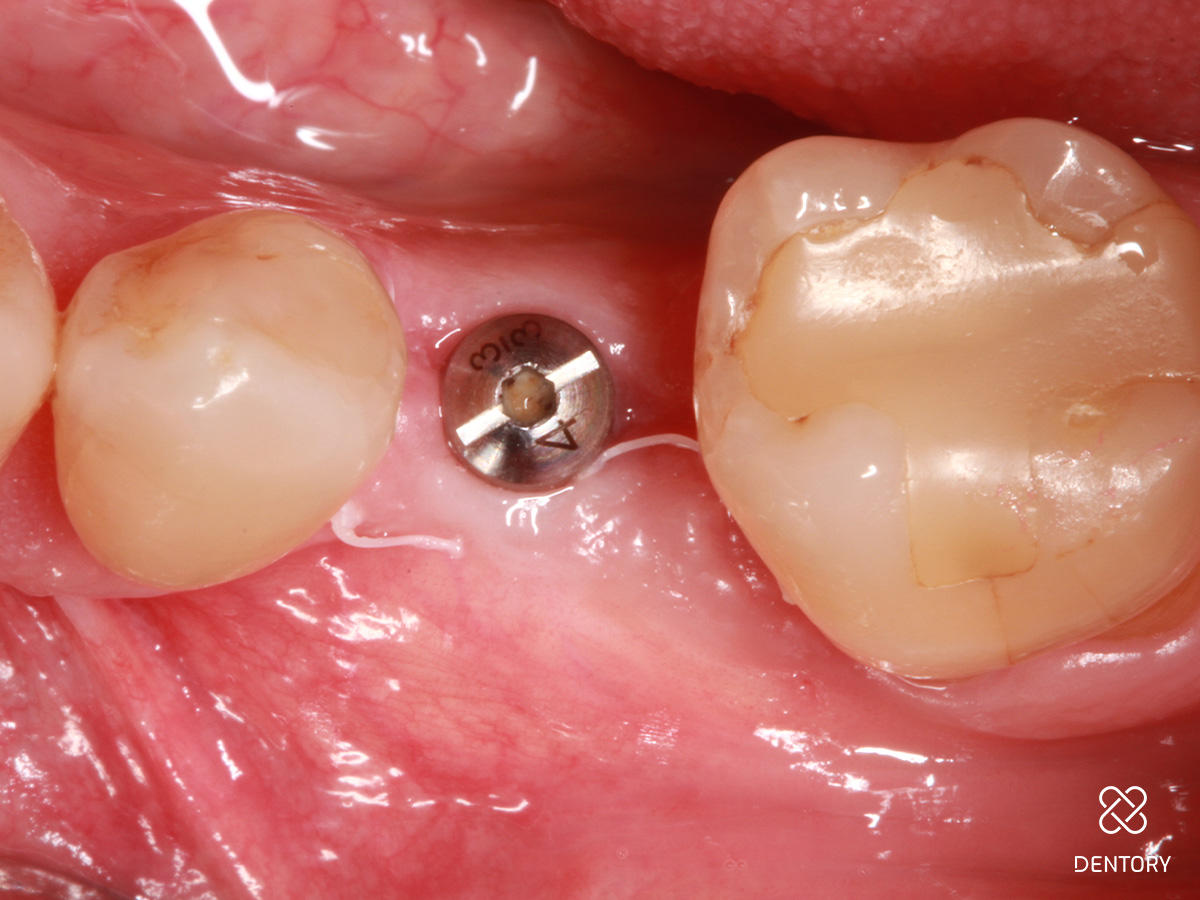

Abbildung 3

Okklusale Ansicht nach Insertion eines 4 mm-Implantats mit Plattform-Switching. Eine simultane Defektrekonstruktion erscheint möglich.